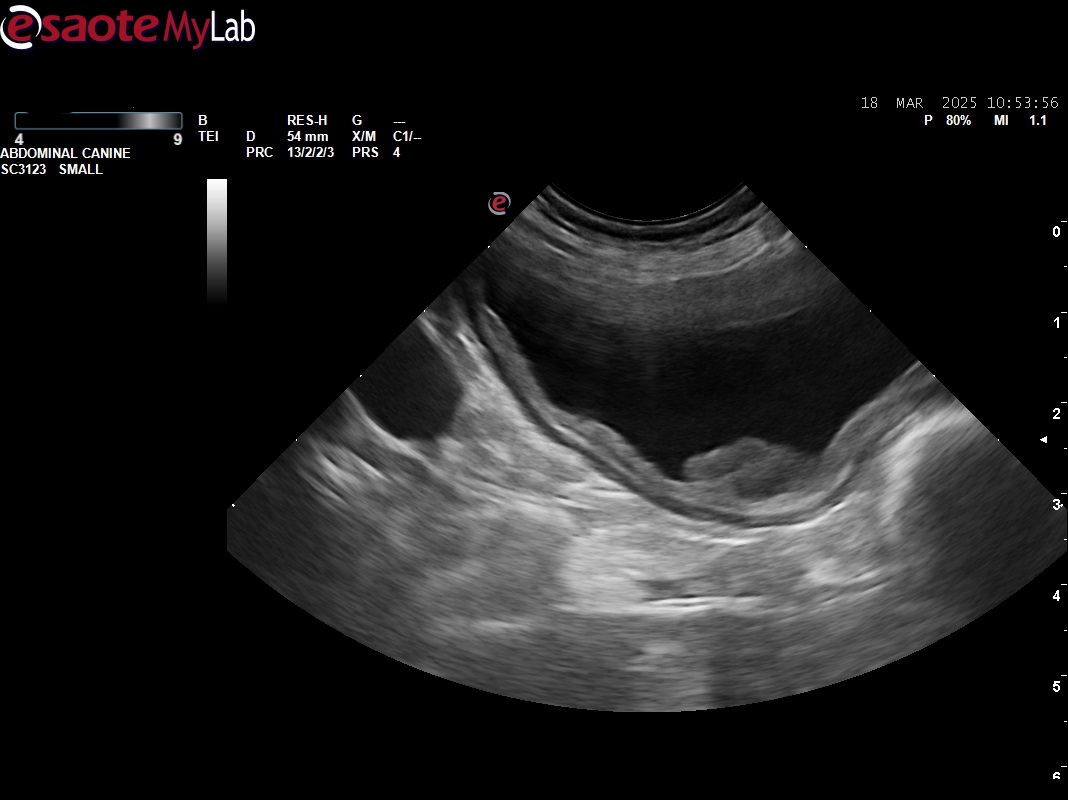

- hyperplázia steny močového mechúra s útvarom vyrastajúcim zo steny